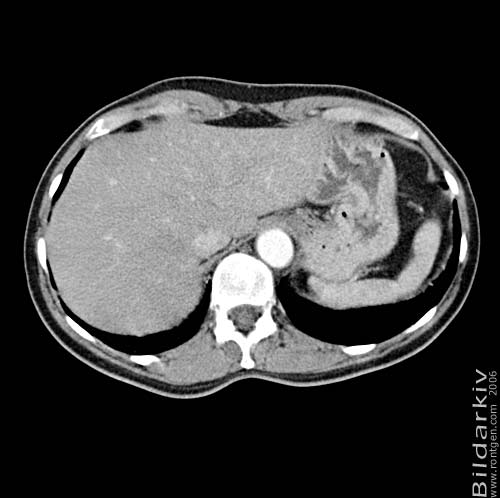

Thorax 51

Snitt över thorax med kontrast. Sk. mediastinum-fönstersättning.

CT Röntgen Helsingborgs lasarett